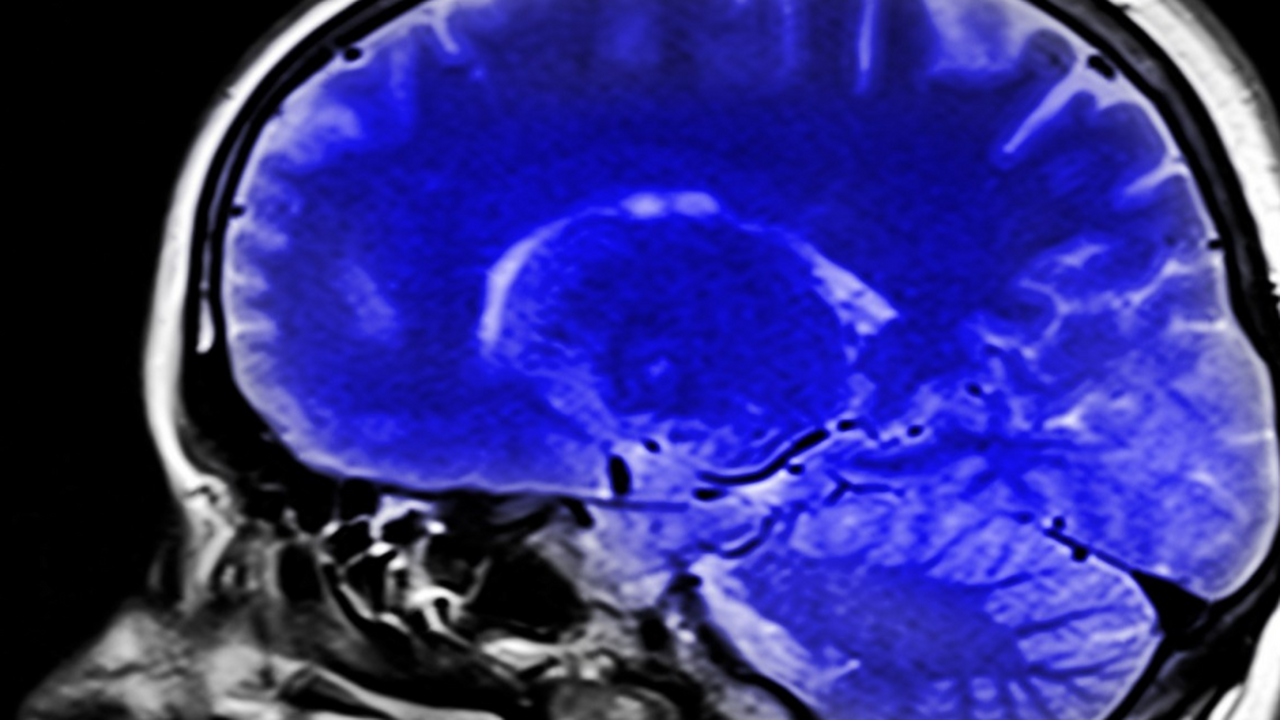

Назван легкий метод выявить первые признаки деменции

Исследователи из центра Baycrest совместно с учёными Торонтского и Йоркского университетов выяснили, что особенности повседневной речи могут служить важным показателем состояния мозга.